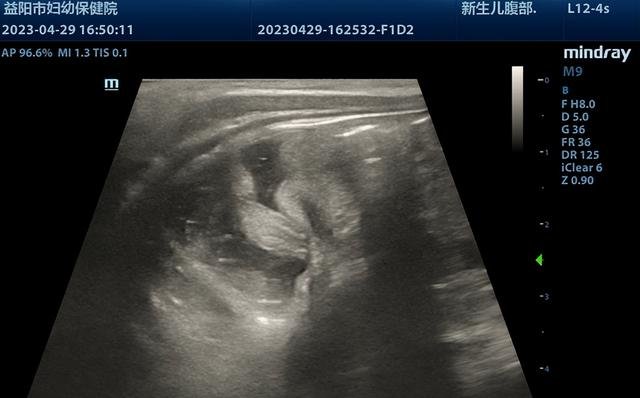

近日,一名仅11个月的小宝宝因呕吐1天来益阳市妇幼保健院就诊,经超声检查可见肠套叠特异征象“套筒征”及“同心圆征”,套入部分肠管长度较长,约60mm,诊断为回结型肠套叠。

超声实时监视下,见生理盐水缓缓充盈结肠至回肠套叠部位。由于患儿套入肠管较长,经操作医生辅以手法按摩,套入回盲部肠管缓慢退出,回盲瓣成功开放,小肠进液,复位成功。整个过程不到半小时。